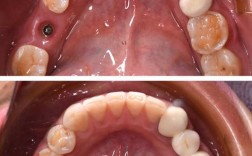

(图片来源网络,侵删)